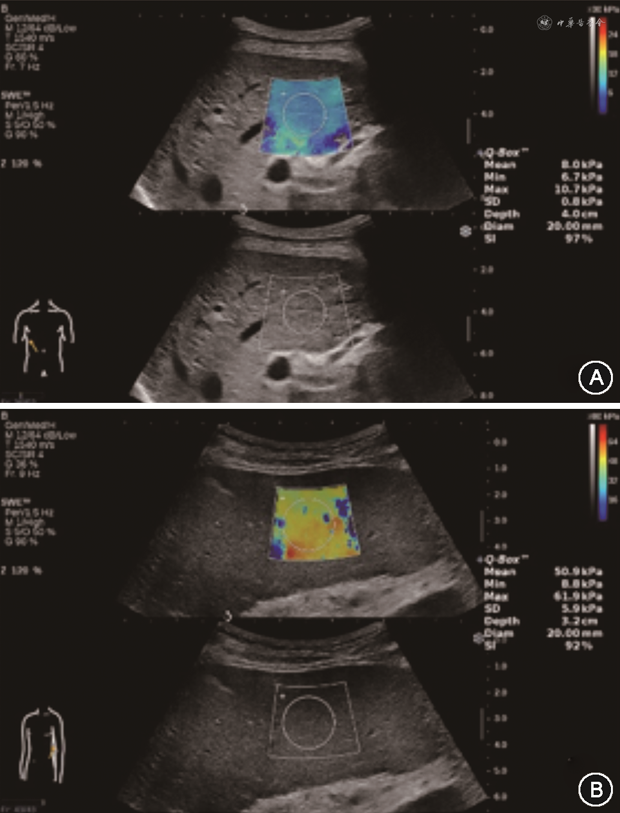

2D-SWE和p-SWE测量时,取样框应置于肝脏实质回声均匀处,避开大血管、胆道及肋骨,取样框尽量平行于肝包膜,放置在肝包膜下方1~2 cm,不超过6 cm处[30, 31, 32,34]。2D-SWE测量LSM时,取样框内填充的彩色信号需超过三分之二,Q-Box优先放置在弹性图的中央位置,建议Q-Box直径≥1.5 cm[31, 32](图1A,图2A)。

(2)测量SSM:被检者仰卧位或轻度右侧倾斜,左臂抬高充分外展,探头垂直于皮肤表面呈90°并适当加压。以灰阶超声图像为基础的p-SWE和2D-SWE测量SSM方法同LSM,取样框尽量平行于脾包膜,放置在脾包膜下方1~2 cm,不超过6 cm处[30,34]。2D-SWE测量SSM时,优先选择脾脏下极,取样框内填充的彩色信号需超过三分之二,Q-Box优先放置在弹性图的中央位置,建议Q-Box直径≥1.0 cm[34,37](图1B,图2B)。